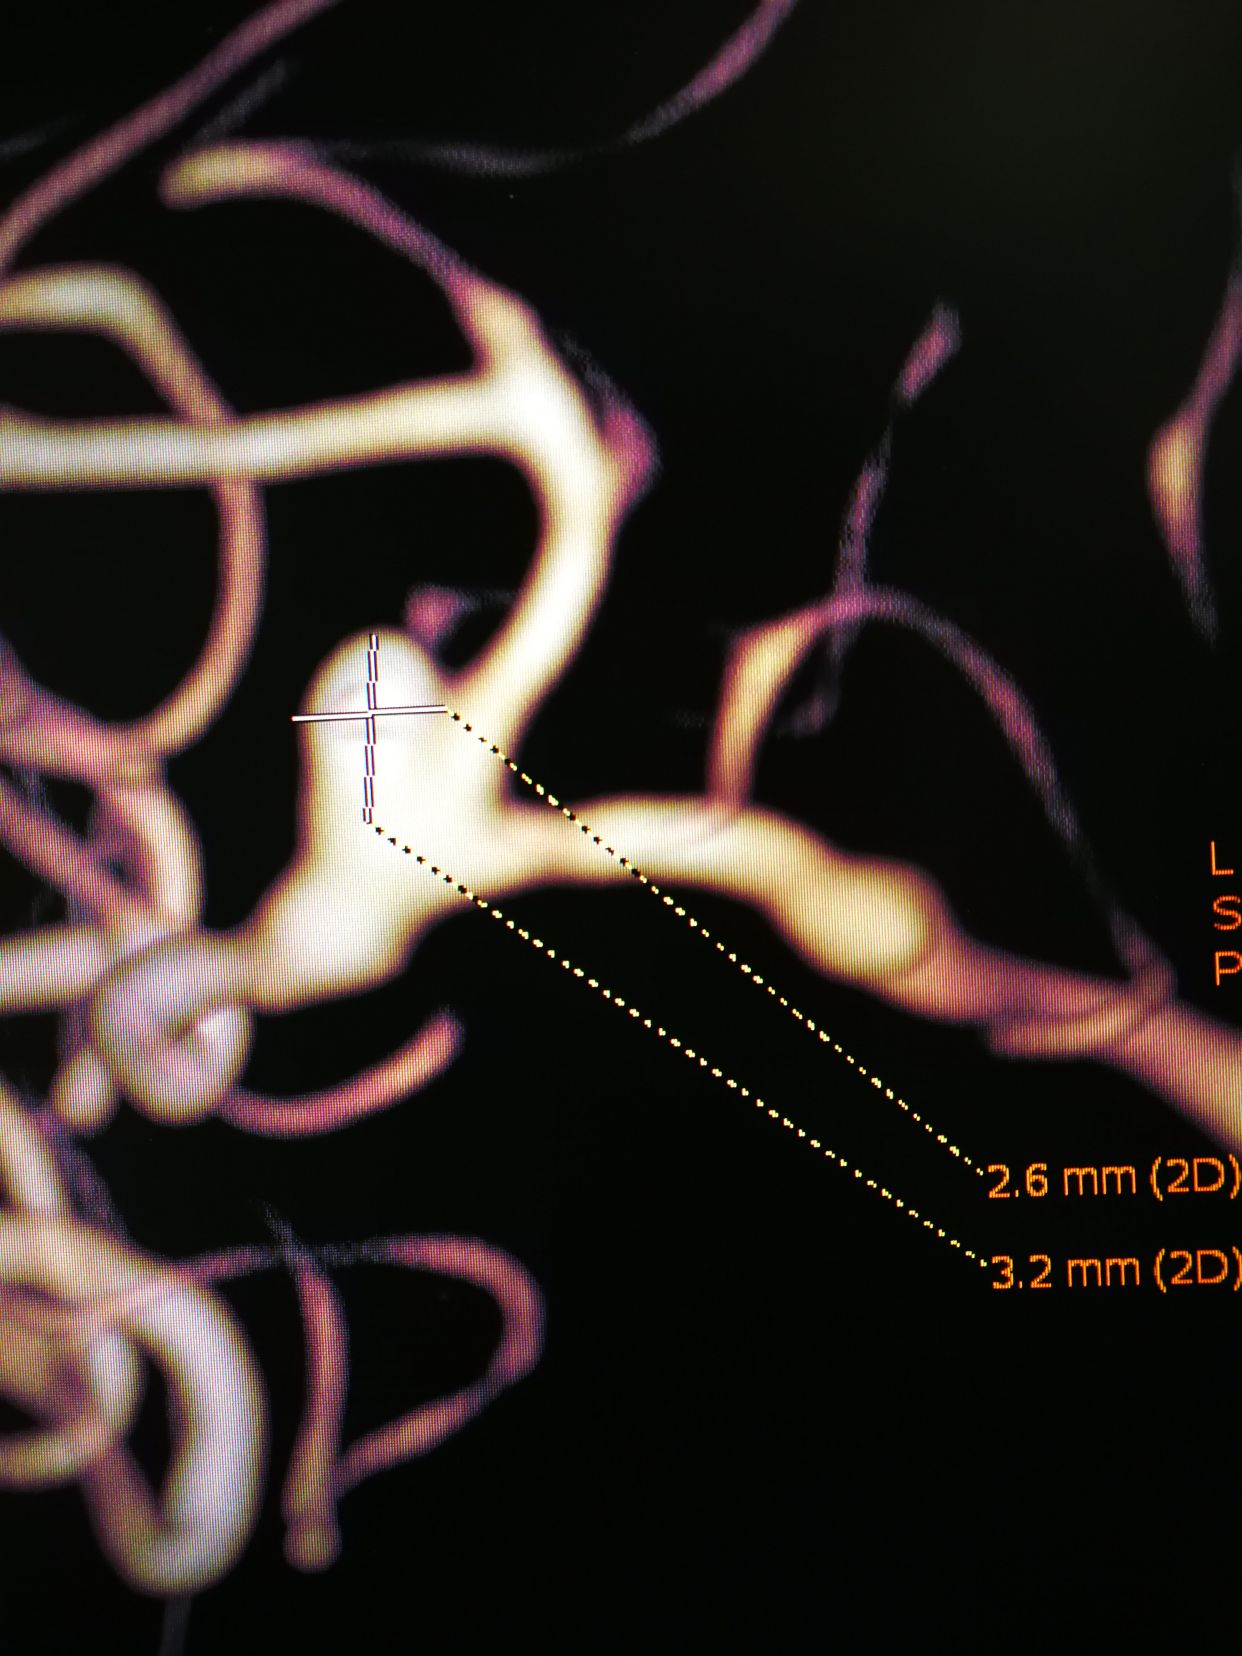

CTA示右侧大脑中分叉部动脉瘤,瘤子小,颈宽,主要累及下干,颈内动脉预期

术前3d和工作位

comos 3-6,hypersoft 1.5-3填塞后,成篮还不错,下干几个袢,支架后释放很放心

lvis25-17,支架打开很好,术后动脉瘤完全不显影。1个半小时结束战斗,收工回家。